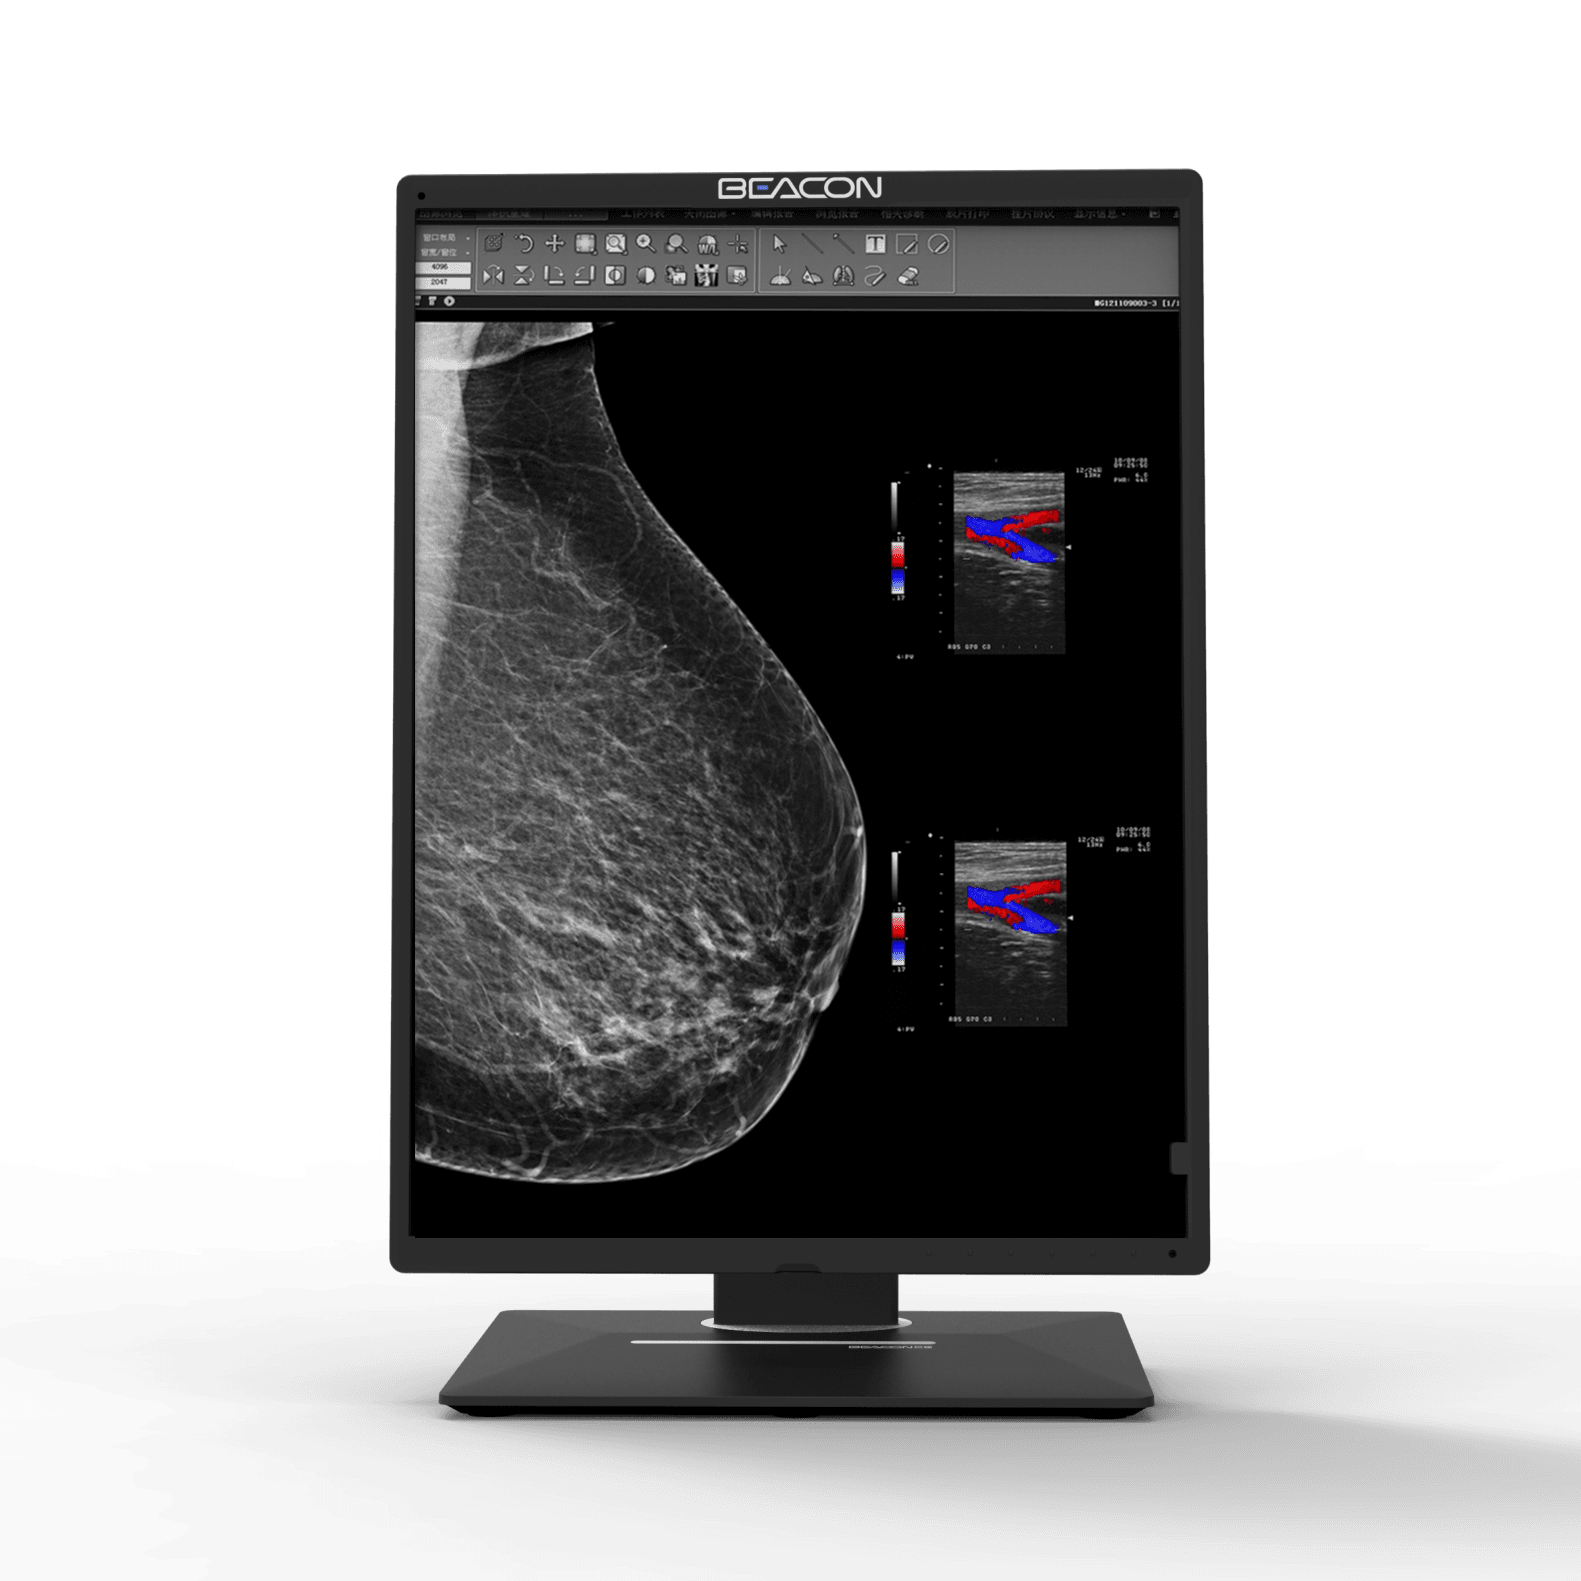

C510S

Tamaño de la pantalla:21.3”

Resolución resolución:2560×2048

C510S tiene funciones de imagen en color y escala de grises, 5 millones de píxeles de resolución ultra alta, brillo ultra alto, contraste ultra alto, amplio ángulo de visión y bajo consumo de energía. Puede ser ampliamente utilizado en varios equipos de imágenes médicas incluyendo mama digital y sistema de PACS.